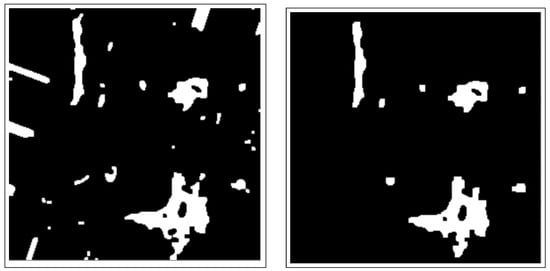

- Morphology operations enhance the image by highlighting important features. The connected components analysis method is used to group components with similar characteristics and assist in separating overlapping and non-overlapping objects.

3.3.1. Connected Components Analysis

3.3.2. Active Contours Segmentation